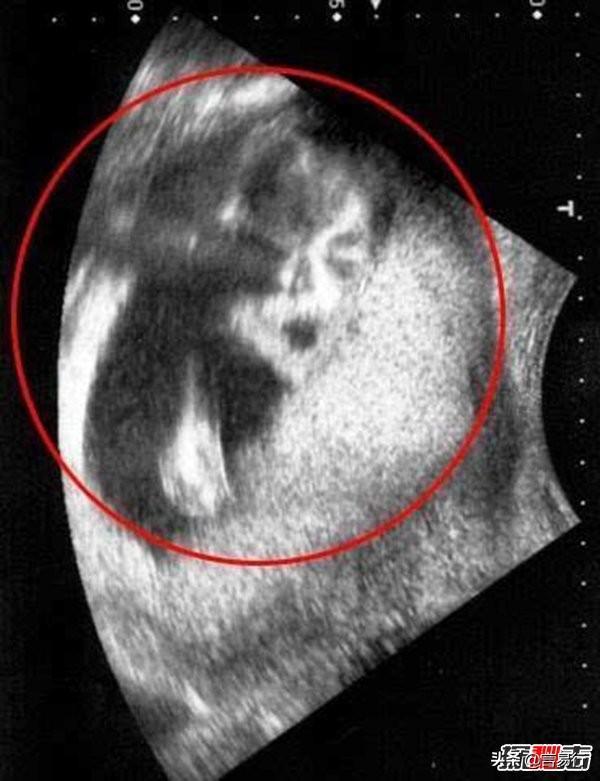

8、B超中发现迈克杰克逊的脸

2009年的11月,在英国有一对夫妇去医院为胎儿进行B超检查,竟然发现B超照片上有已经去世的歌王迈克杰克逊的脸,这让他们惊呆了。

他们立即去临近的格林顿·雷恩便利中心进行更仔细的检查。但是当扫描结果出来后夫妇两人被惊得目瞪口呆片子上已故歌王迈克尔·杰克逊正两眼直勾勾地“盯着”他们。

孕妇道恩·凯莉已经是6个孩子的母亲了,她说以前从来没发生过这种事情,感到的诡异。